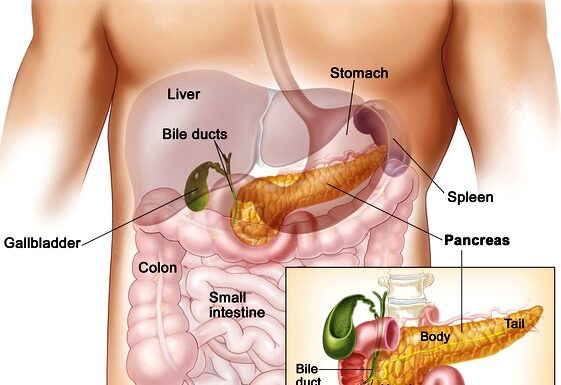

Νέα θεραπευτική αγωγή για τον προχωρημένο καρκίνο του παγκρέατος

Ο καρκίνος του παγκρέατος αποτελεί την τέταρτη αίτια θνητότητας από καρκίνο παγκοσμίως. Τα τελευταία χρόνια διαπιστώνεται μία αύξηση στην επίπτωσή του. Λόγω της θέσεως του παγκρέατος, συχνά αυτός ο καρκίνος δεν έχει συμπτωματολογία στα αρχικά του στάδια. Αποτελεί μία σιωπηλή νόσο με το 80%...

Παγκόσμια ημέρα κατά του καρκίνου του παγκρέατος

Η τρίτη Πέμπτη του Νοεμβρίου κάθε έτους έχει καθιερωθεί ως «Η παγκόσμια ημέρα κατά του καρκίνου του παγκρέατος» και έχει ως στόχο την ευαισθητοποίηση του κοινού για την συγκεκριμένη κακοήθεια.

Ο καρκίνος του παγκρέατος αποτελεί την τέταρτη σε θνητότητα κακοήθεια στην Ευρώπη καθώς ευθύνεται για...